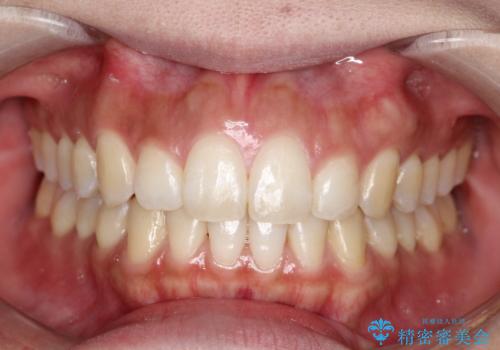

目立たない矯正で八重歯を改善

今回の矯正治療では、透明なマウスピース型の装置インビザラインを使用しました。この装置は目立ちにくく、取り外しが可能なため、食事や歯磨きも普段通りに行えます。遠心移動という方法で奥歯を後方に動かし、前歯を並べるためのスペースを確保。これにより、抜歯することなく、左上の八重歯を含む叢生を効果的に改善し、整った美しい歯並びと良好な咬み合わせを獲得していただけました。